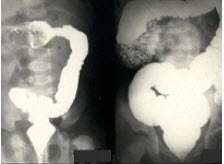

24、单项选择题

女,2岁半,突然哭闹3小时,急性面容,腹部触诊上腹区似可扪及包块,行钡灌肠检查,如图所示,最可能的诊断为()

A.肠套叠

B.先天性巨结肠

C.结肠扭转

D.结肠炎

E.结肠癌